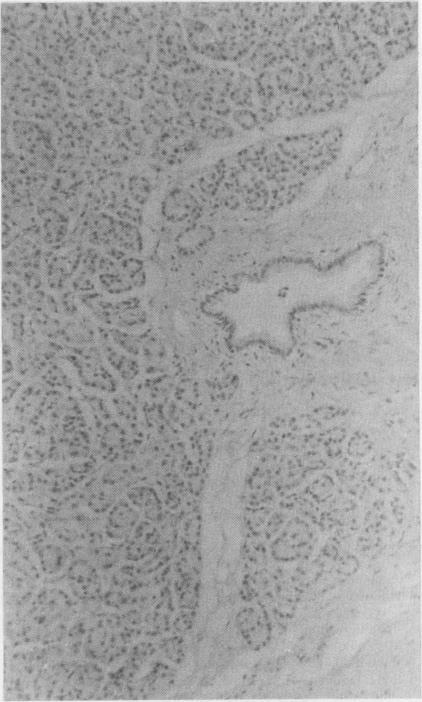

Lectin peroxidase histochemical analysis was carried out on pancreatic tissue from patients with pancreatic carcinoma and chronic pancreatitis and from subjects with normal pancreas to find a tumour specific pattern of lectin binding that would aid histological and cytological diagnosis. There were striking differences between the lectin binding characteristics of the different cell types in the normal pancreas. Acinar cells were uniformly positive for binding with wheat germ agglutinin and soy bean agglutinin while islet cells were usually negative for these lectins. Ulex europaeus I lectin however, was found not to be specific for endothelium, showing positivity also for acinar and ductal tissue. Griffonia simplicifolia II lectin was found to be highly specific for ductal epithelium, and because of this was tested in a hamster pancreatic cancer model where it was not specific for ductal epithelium, reflecting differing carbohydrate expression in the hamster pancreas. Pancreatic carcinomas and chronic pancreatitis bound all five lectins without any qualitative distinction from each other or from normal pancreatic tissue, but there was increased intensity of peanut agglutinin binding to secreted mucins in pancreatic carcinoma, which may be of potential use in radiolabelled lectin scanning.

对胰腺癌患者、慢性胰腺炎患者以及胰腺正常者的胰腺组织进行了凝集素过氧化物酶组织化学分析,以寻找有助于组织学和细胞学诊断的肿瘤特异性凝集素结合模式。正常胰腺中不同细胞类型的凝集素结合特征存在显著差异。腺泡细胞与麦胚凝集素和大豆凝集素结合呈均匀阳性,而胰岛细胞对这些凝集素通常呈阴性。然而,发现荆豆凝集素I并非内皮细胞特异性的,腺泡和导管组织也呈阳性。发现西非单叶豆凝集素II对导管上皮具有高度特异性,因此在仓鼠胰腺癌模型中进行了测试,结果显示它对仓鼠胰腺的导管上皮不具有特异性,这反映了仓鼠胰腺中碳水化合物表达的差异。胰腺癌和慢性胰腺炎对所有五种凝集素的结合没有相互之间或与正常胰腺组织的任何定性区别,但胰腺癌中花生凝集素与分泌性粘蛋白的结合强度增加,这可能在放射性标记凝集素扫描中具有潜在用途。